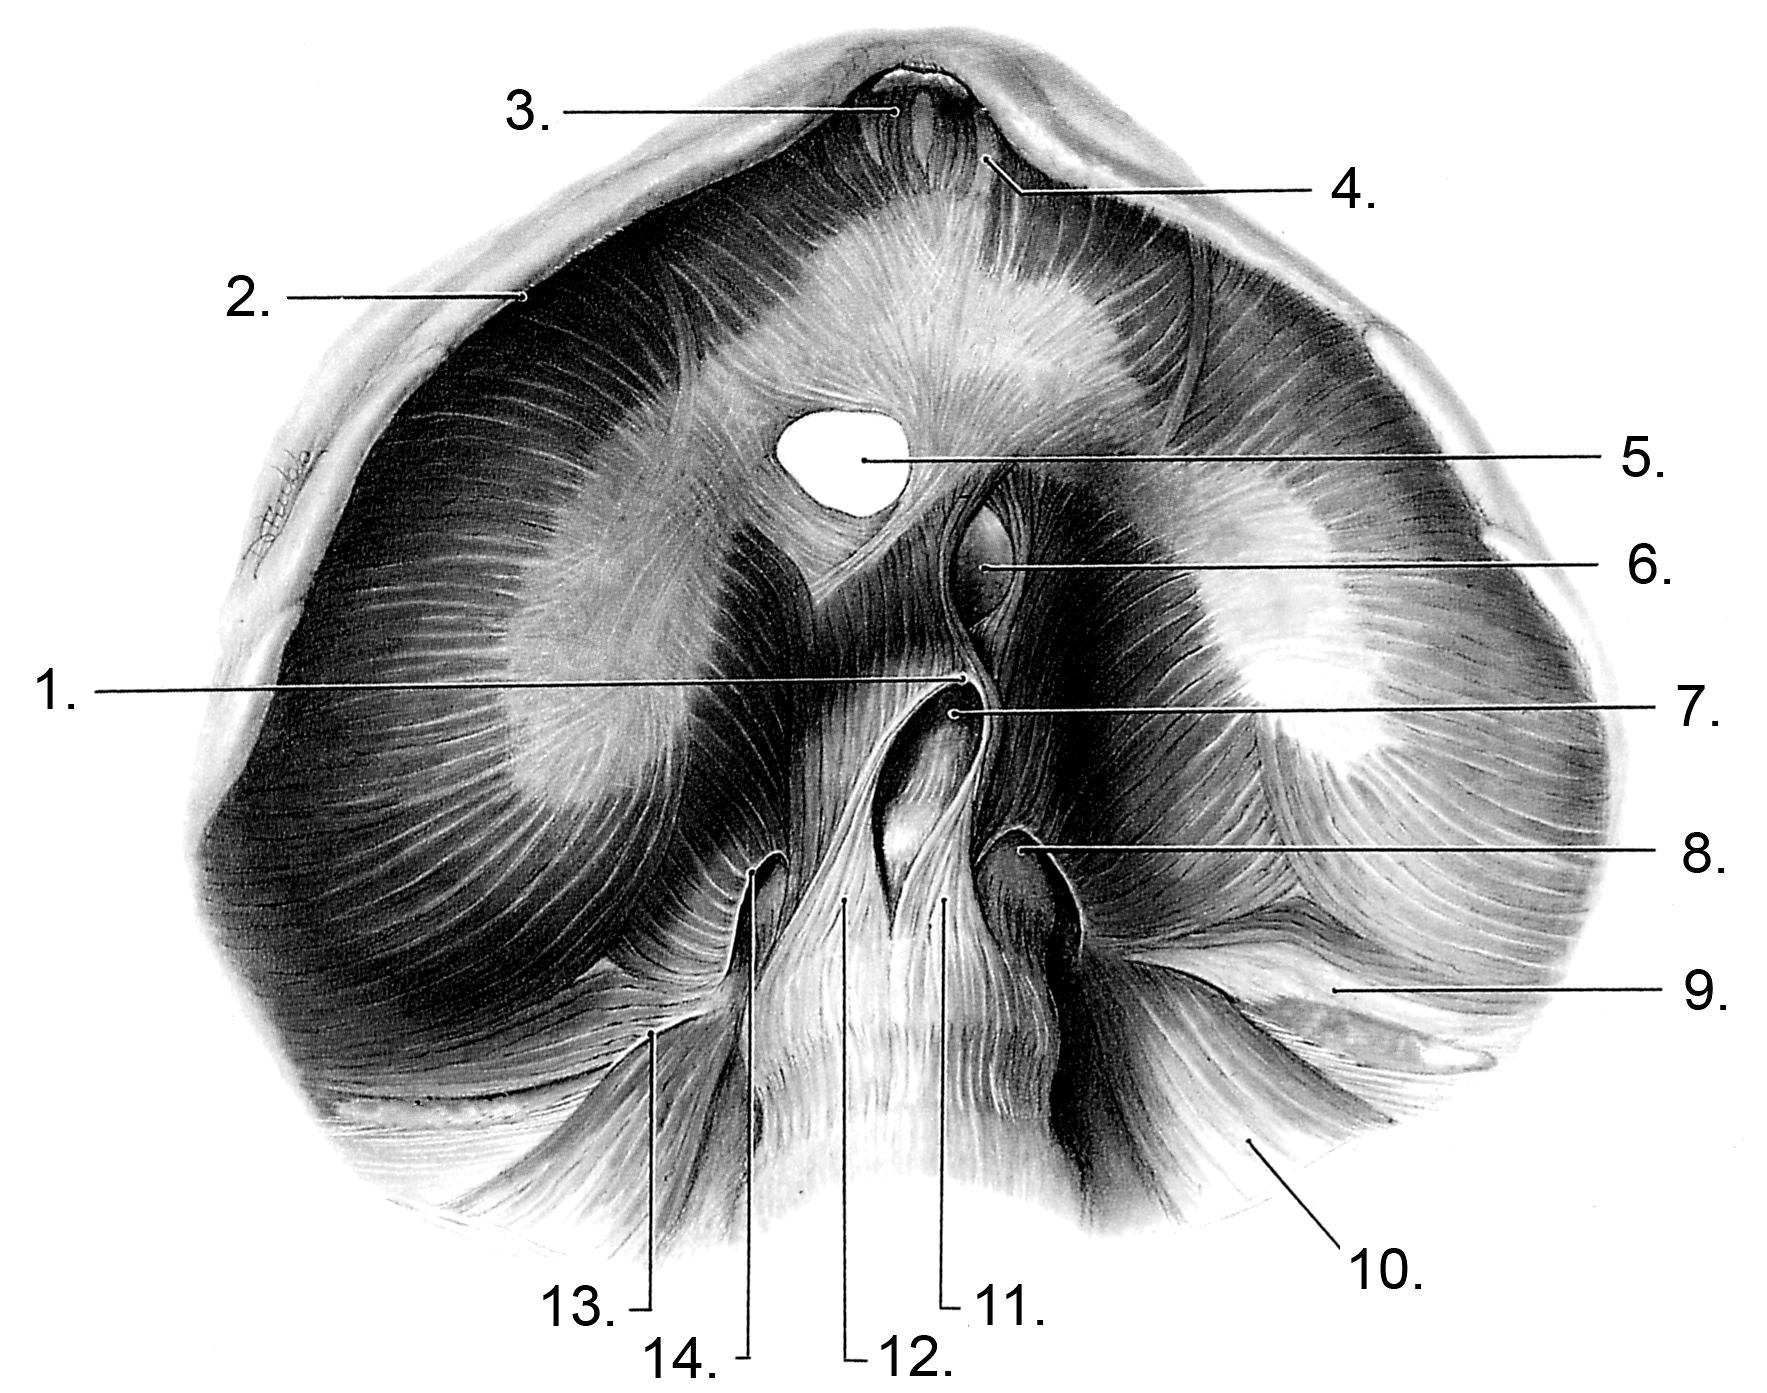

Анатомия диафрагмы и треугольника Бохдалека